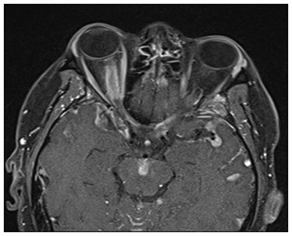

CSF analysis revealed elevation of protein (38mg/ml) and WBC count (710/ml). Flow cytometry was consistent with plasma cell myeloma (Figure 3). Fluorescence in situ hybridization (FISH) analysis demonstrated deletion of chromosome 13q in 78.5% of cells, monosomy of chromosome 17 in 87% of cells and gain of 1q in chromosome 71 of 5% of cells. The patient received 12 sessions of whole brain irradiation and intrathecal chemotherapy with methotrexate/cytarabine/hydrocortisone over the course of two weeks. However, there was no improvement of vision in the right eye. Vision in the left eye fluctuated between 20/32 and 20/100 during his two weeks of admission without any disc edema. Vision in the left eye recovered to baseline after completion of treatment. He also did not develop any new neurologic symptoms.

Figure 3 Cell cytology from lumbar puncture, displaying atypical morphology with blastic features.